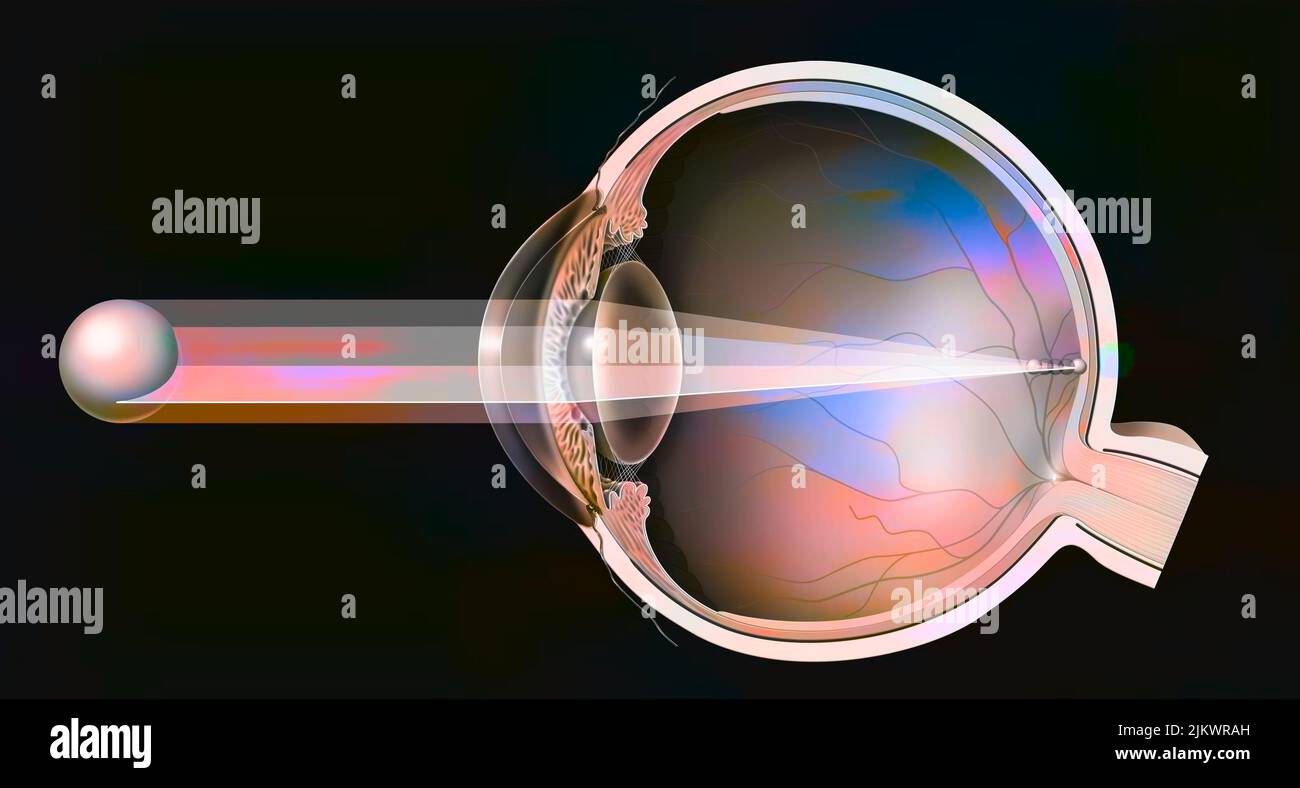

RF2JKWT9A–Oeil, cataracte, phacoémulsification - étape 2: Consiste à casser la lentille avec une sonde.